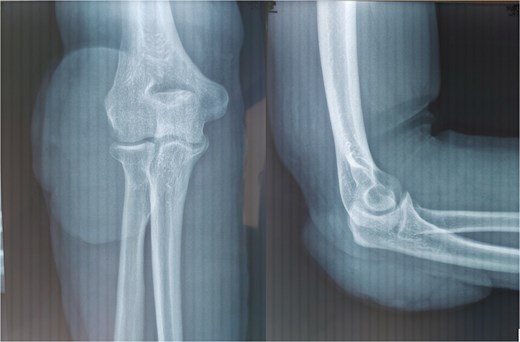

The patient underwent a standard radiograph of the elbow, in front and in profile, showing no bone involvement and demonstrating the presence of a superficial extra-osseous oval opacity with a long vertical axis, with clean margins and no calcification, located posterolateral to the elbow. Surgical biopsy and histological study led to the diagnosis of pilomatricoma, with vasculoexudative inflammatory changes in the overlying skin tissue and no histological signs of malignancy (Fig. 2).